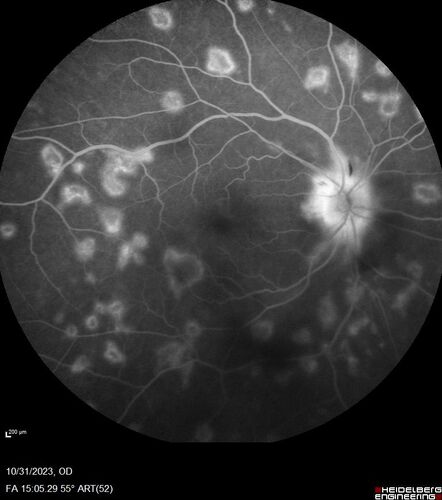

Serpiginous choroiditis in the right eye

68 year old female with spots in vision in the right eye for 2 months.  She has a history of MS.  The vision is 20/32 in both eyes.  She was treated with high dose steroids and transitioned to methotrexate and the right eye quieted  down.